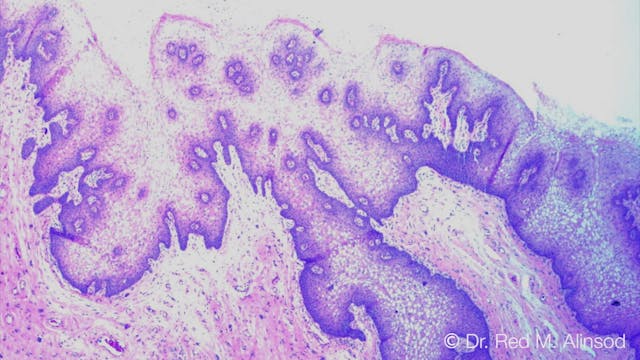

Vulvar Biopsy of Lichen Sclerosus Treated with PRP and Amniotic Fluid

AIAVS Fellows Video 30, Live Narrated Vulvar Biopsy and PRP + AmDrop Injection Platelet Rich Plasma